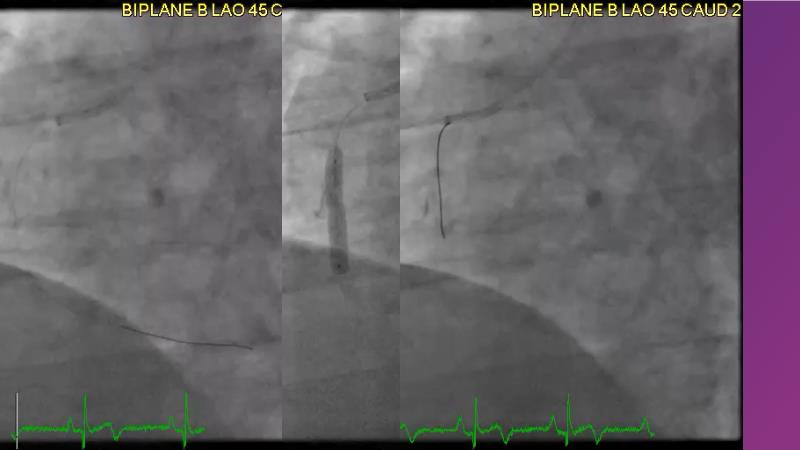

Tune into this 2024 session for insights into the latest ESC guidelines, strategies to prevent and treat no reflow, and an examination of trials like TASTE, TAPAS, and TOTAL on coronary thrombus management. Explore also the outcomes of the CHEETAH study, pondering a potential paradigm shift, and delve into a case study on thrombus removal in a patient with high thrombus burden.